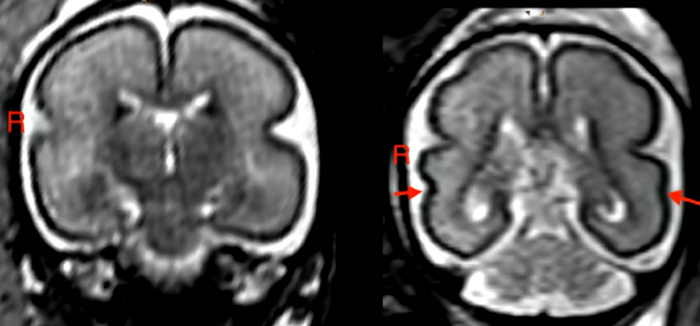

In fetuses with alcohol exposure, the fetal total maturation score (fTMS) was significantly lower than in the age-matched controls, and the right superior temporal sulcus (STS) was shallower. The STS is involved in social cognition, audiovisual integration and language perception.

“We found the greatest changes in the temporal brain region and STS,” Dr. Kasprian said. “We know that this region, and specifically the formation of the STS, has a great influence on language development during childhood.”

According to the researchers, delayed fetal brain development could be specifically related to a delayed stage of myelination and less distinct gyrification in the frontal and occipital lobes.

Gyrification refers to the formation of the folds of the cerebral cortex. This folding enlarges the surface area of the cortex with limited space in the skull, enabling an increase in cognitive performance. When gyrification is diminished, functionality is reduced.